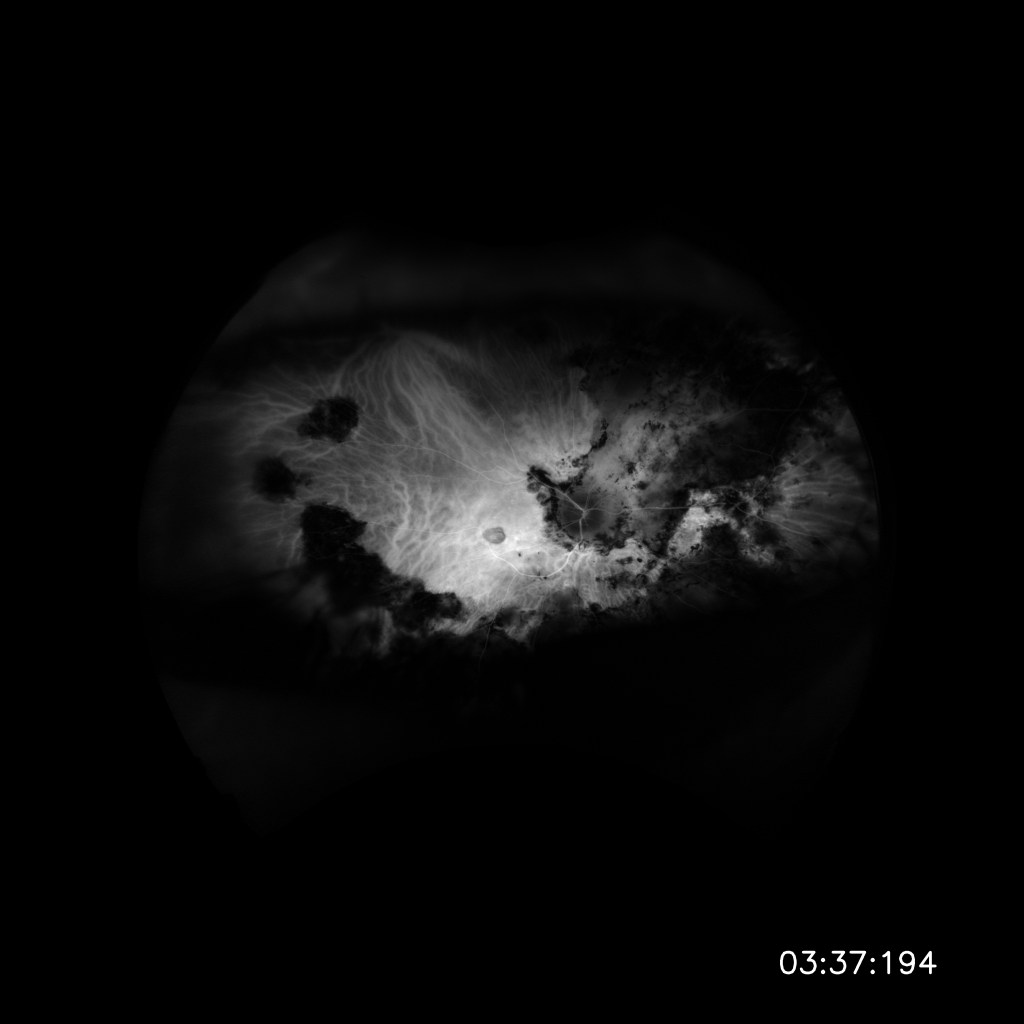

Bottom Image: My right eye with tons of lesions and scaring from past inflammation due to uveitis. These are the areas that I cannot see through when they are in my field of vision. (8/28/2020)